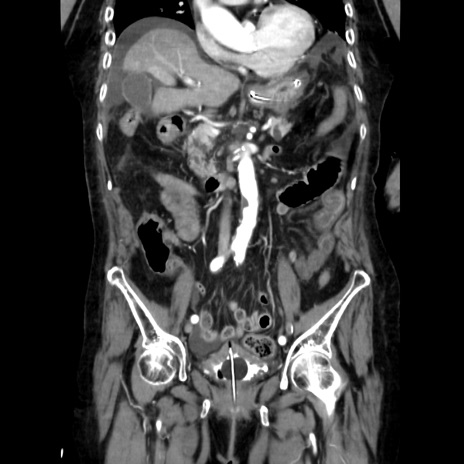

症例40(冠状断像)

冠状断像